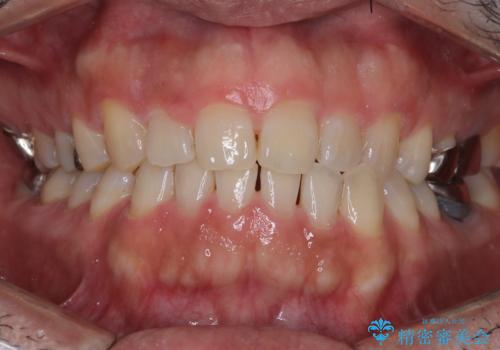

八重歯と正中のズレを解消!目立ちにくいワイヤー矯正で美しい歯並びへ

担当医 河口智英